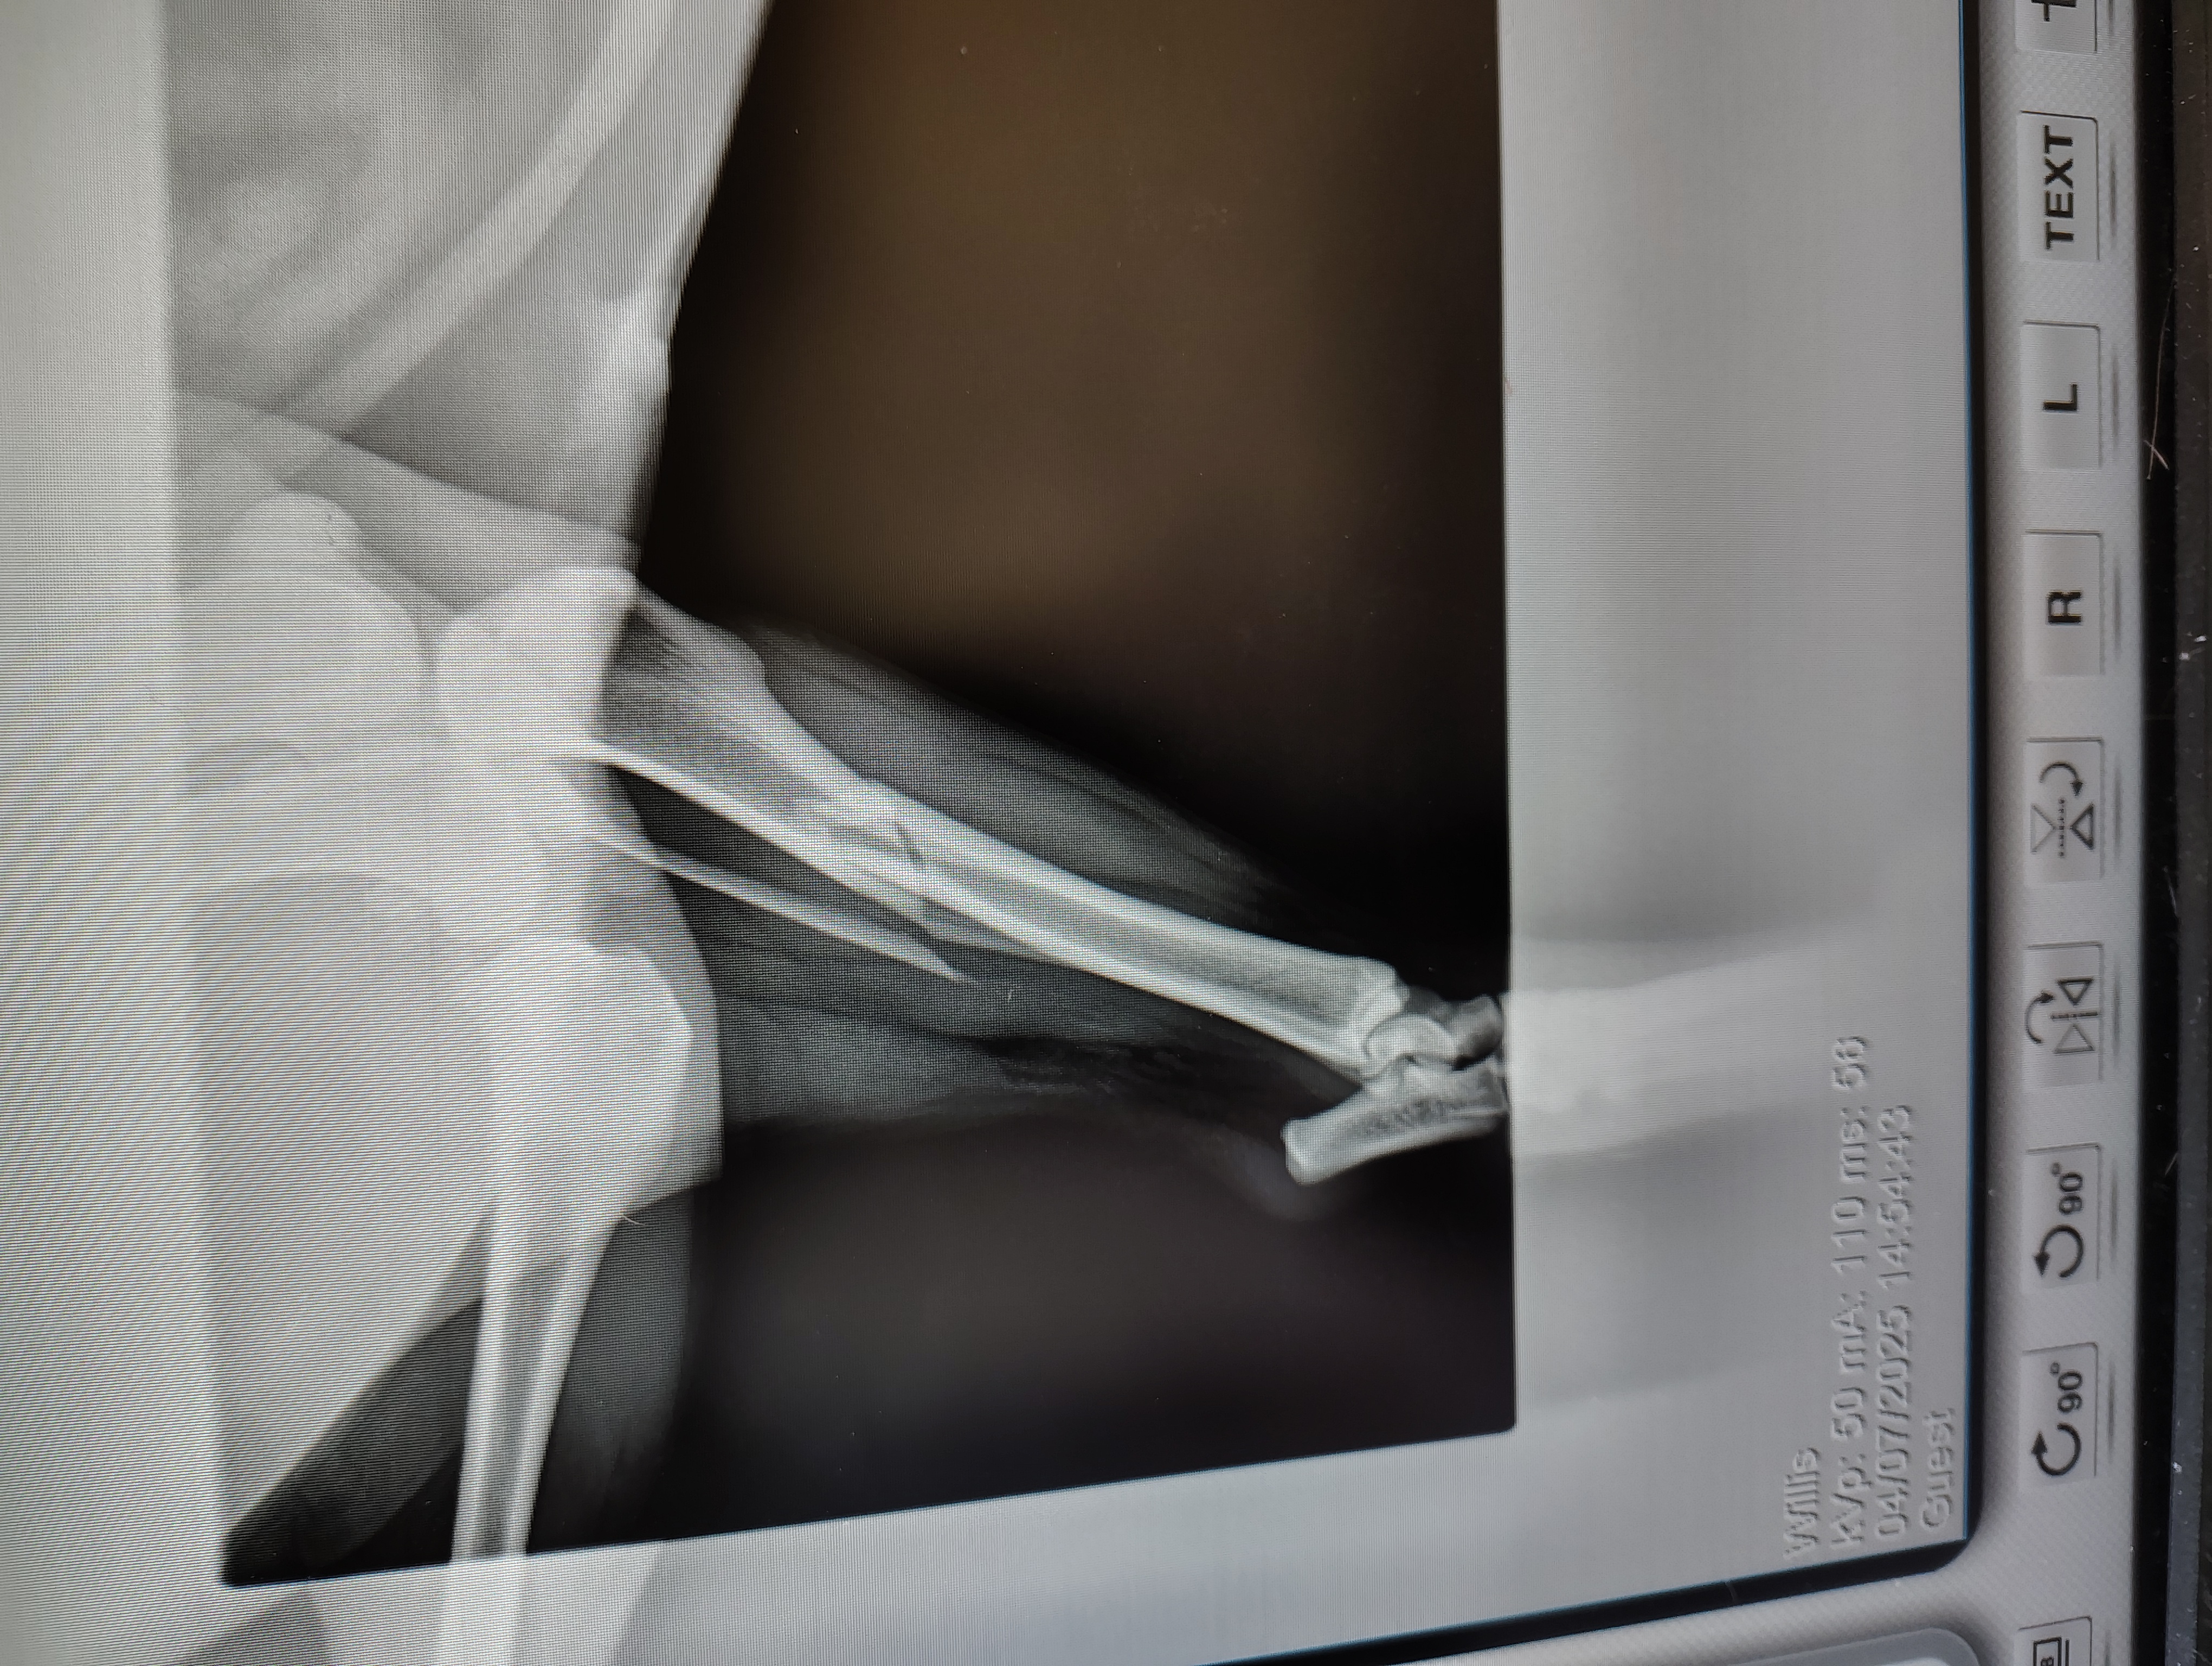

Hi, my name is Heather and my dog Ripley broke her leg while playing with her brother, and the vet says she needs surgery to put a plate on it for proper healing. We rescued her a little over a year and a half ago. The surgery estimate is $2000. Anything you can help with will be much appreciated, we are trying to get help with $1000. Thank you.